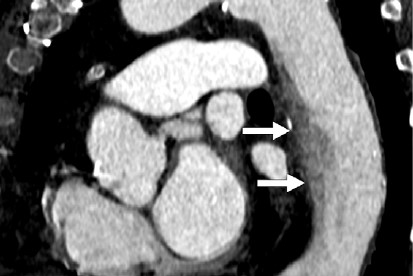

The group compared the performance of ultrahigh-resolution CTA (slice thickness down to 0.25 mm and spatial resolution of up to 50 lp/cm) to conventional CTA for detecting and characterizing intracranial aneurysms via a study that included 108 patients with atraumatic subarachnoid hemorrhage who underwent digital subtraction angiography (DSA) and either ultrahigh-resolution CTA or conventional CTA.

The team found that ultrahigh-resolution CTA had higher image quality and diagnostic confidence for all readers – and lower effective radiation dose (p < 0.001).

Specificity was comparable between the two techniques, Frenzel and colleagues wrote. They also noted that both CT dose index-volume and dose length product (and therefore, estimated effective dose) were lower on ultrahigh-resolution CTA compared to conventional CTA (p ≤ 0.001).